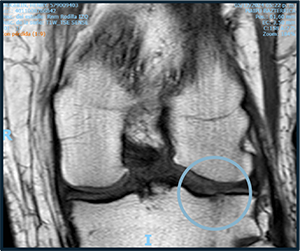

PRE TREATMENT

November 5, 2023

POST TREATMENT

November 10, 2024